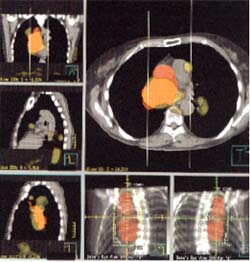

PLANIFICACION DE RADIOTERAPIA.

Ya que el estudio de PET puede detectar un tumor maligno o sus metástasis, se puede utilizar este mismo estudio, en indicar la dosis de radiación a administrar por medio de software específicos, sin necesidad de someter al paciente a mas estudios.

Esto se realiza sólo por medio de equipos PET-CT, ya que es posible definir con mucha exactitud la dosis de radiación que requerirá un tumor maligno definiendo la actividad metabólica tumoral junto, con al análisis anatómico. Determinar la dosis exacta no siempre es simple en su cálculo con los medios tradicionales, por lo que la utilización de esta técnica, es de gran ayuda para el radioterapeuta.

Contornos de planificación de Radioterapia basados sólo en TAC en color rojo, comparados con los de PET F-18FDG en amarillo. Es posible ver que sin las imágenes de PET múltiples focos tumorales que no aparecen para irradiar a la TAC.